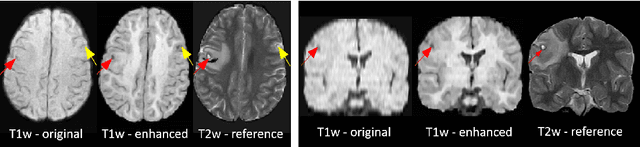

Abstract:Low-field (<1T) magnetic resonance imaging (MRI) scanners remain in widespread use in low- and middle-income countries (LMICs) and are commonly used for some applications in higher income countries e.g. for small child patients with obesity, claustrophobia, implants, or tattoos. However, low-field MR images commonly have lower resolution and poorer contrast than images from high field (1.5T, 3T, and above). Here, we present Image Quality Transfer (IQT) to enhance low-field structural MRI by estimating from a low-field image the image we would have obtained from the same subject at high field. Our approach uses (i) a stochastic low-field image simulator as the forward model to capture uncertainty and variation in the contrast of low-field images corresponding to a particular high-field image, and (ii) an anisotropic U-Net variant specifically designed for the IQT inverse problem. We evaluate the proposed algorithm both in simulation and using multi-contrast (T1-weighted, T2-weighted, and fluid attenuated inversion recovery (FLAIR)) clinical low-field MRI data from an LMIC hospital. We show the efficacy of IQT in improving contrast and resolution of low-field MR images. We demonstrate that IQT-enhanced images have potential for enhancing visualisation of anatomical structures and pathological lesions of clinical relevance from the perspective of radiologists. IQT is proved to have capability of boosting the diagnostic value of low-field MRI, especially in low-resource settings.

Abstract:1.5T or 3T scanners are the current standard for clinical MRI, but low-field (<1T) scanners are still common in many lower- and middle-income countries for reasons of cost and robustness to power failures. Compared to modern high-field scanners, low-field scanners provide images with lower signal-to-noise ratio at equivalent resolution, leaving practitioners to compensate by using large slice thickness and incomplete spatial coverage. Furthermore, the contrast between different types of brain tissue may be substantially reduced even at equal signal-to-noise ratio, which limits diagnostic value. Recently the paradigm of Image Quality Transfer has been applied to enhance 0.36T structural images aiming to approximate the resolution, spatial coverage, and contrast of typical 1.5T or 3T images. A variant of the neural network U-Net was trained using low-field images simulated from the publicly available 3T Human Connectome Project dataset. Here we present qualitative results from real and simulated clinical low-field brain images showing the potential value of IQT to enhance the clinical utility of readily accessible low-field MRIs in the management of epilepsy.